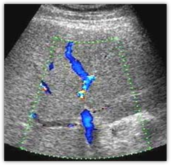

3. Доплерівська ультрасонографія

Можна виявити кровотік в круглій зв’язці печінки при реканалізації параумбі-лікальної вени, а також візуалізувати інші порто-системні колатералі.